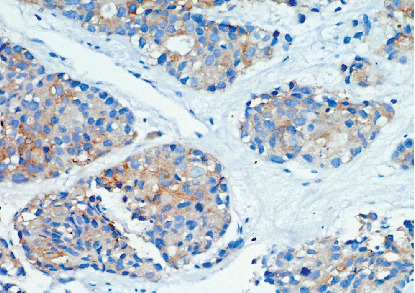

大细胞神经内分泌癌(LCNEC)是一种罕见的侵袭性癌症,主要发生在肺部,但也可以发生在其他器官。它的特点是进展迅速和高转移潜力。我们提出一例晚期LCNEC肺患者表现不佳(PS),需要氧气支持。影像学显示右上叶大肿块,淋巴结病变,伴支气管包膜及侵犯上腔静脉,导致SVC综合征及胸腔积液。活检和免疫组化证实LCNEC。由于患者PS较差,以低剂量单药化疗(卡铂)开始治疗,改善后给予依托泊苷和顺铂治疗。同时给予局部放疗,并调整治疗计划纳入atezolizumab。10个周期后,患者完全缓解,持续6年。该病例强调了老年患者晚期LCNEC管理的复杂性以及多学科方法和免疫治疗的有效性。

Large cell neuroendocrine carcinoma (LCNEC) is a rare, aggressive cancer primarily found in the lungs but can also occur in other organs. It is characterized by rapid progression and high metastatic potential. We present a case of advanced-stage LCNEC lung in a patient with a poor performance status (PS), requiring oxygen support. Imaging revealed a large right upper lobe mass, lymphadenopathy, with bronchial encasement and invasion into the superior vena cava, leading to SVC syndrome and pleural effusion. Biopsy and immunohistochemistry confirmed LCNEC. Due to the patient's poor PS, treatment began with low-dose single-agent chemotherapy (carboplatin), followed by etoposide and cisplatin after improvement. Local radiation was also administered, and the treatment plan was adjusted to include atezolizumab. After 10 cycles, the patient achieved complete remission, sustained for 6 years. This case highlights the complexities of managing advanced LCNEC in a geriatric patient and the effectiveness of a multidisciplinary approach and immunotherapy.